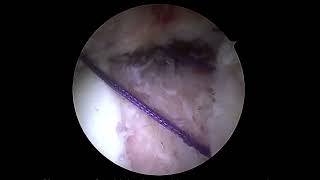

Rotator Cuff Repair And Regeneten Patch

244

4:06